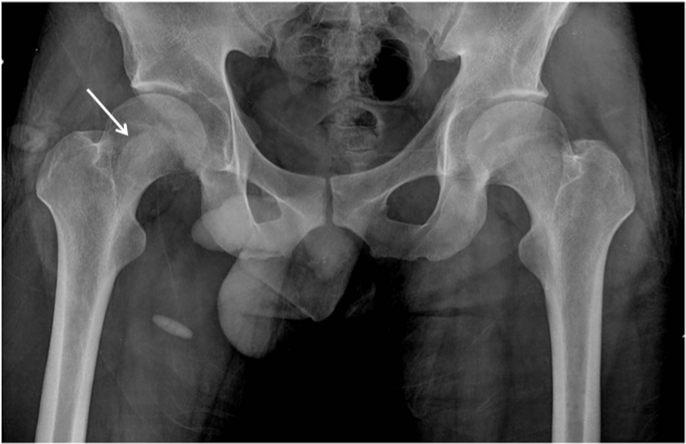

A 27-year-old man was injured by automobile accident and immediately presented to our emergency department. On physical examination, right hip was in flexion, external rotation and abduction. He complained of severe pain, and passive and active movements were not possible in right hip. There was neither neurovascular deficiency nor associated injuries. Radiograph of both hip revealed obturator dislocation of right femoral head and fractured femoral head fragment within hip joint (Figure 1). The dislocation was immediately reduced by traction in line of deformity followed by gentle adduction and internal rotation with pelvis stabilized by an assistant. After closed reduction, anteroposterior radiograph showed femoral head was reduced but crescentic radio-opacity was visible overlying femoral head and translateral radiograph revealed that the fractured femoral head fragment was turned inside out during closed reduction (Figure 2A & 2B). Computed tomogram depicted the 3-D configuration of fracture (Figure 2C & 2D).